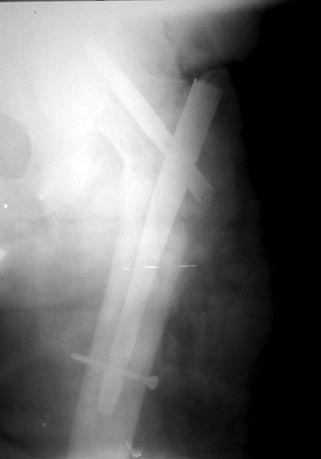

Уважаемые коллеги! На консультацию пришел больной 44-х лет (снимки 1 и 2): упал на улице 26.11.2012г., оперирован в одном из лечебных учреждений 26.11.2012. Сделали контрольные рентгенограммы и КТ. Хотели-бы обсудить варианты оперативного лечения: DHS или БИОС?

Если честно, то на первом снимке отломки "стояли" лучше, чем после "репозиции" и остеосинтеза пресловутой Г-образной пластиной-не восстановлена дуга Адамса, ну или по другому- отсутствие медиальной опоры. По этой же причине не рекомендую DHS, только штифт типа Гамма, при этом обязательно

восстановить шеечно-диафизарный угол, а клинок установить максимально близко к дуге Адамса, до субходральной зоны головки бедр. кости.